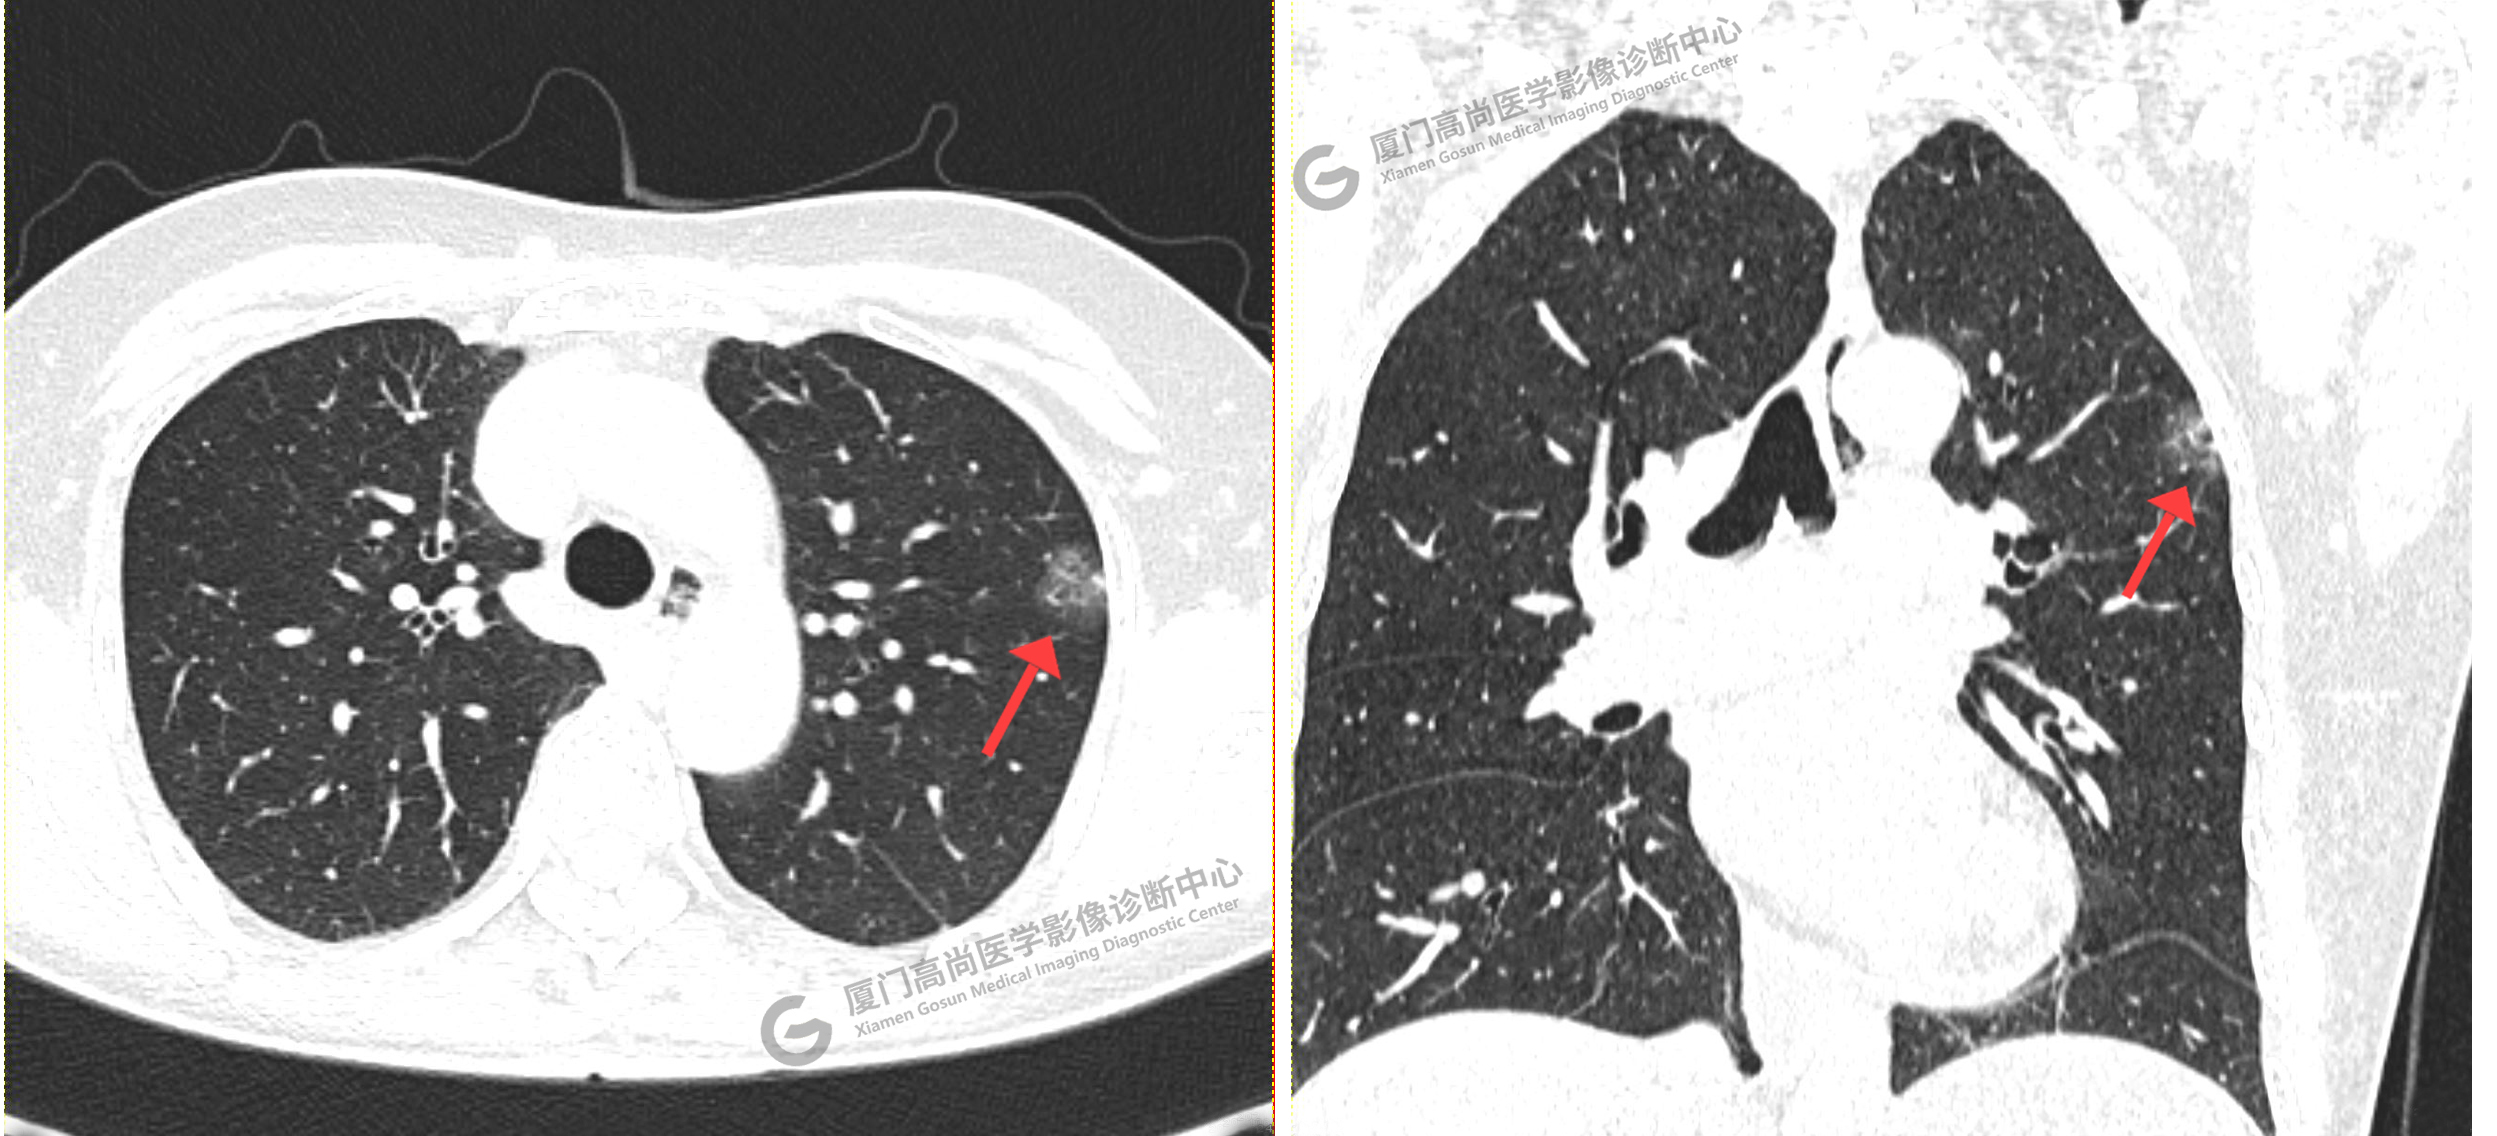

李先生在我中心進(jìn)行個(gè)人體檢,進(jìn)行了胸部CT掃描。

CT影像圖

CT示:左肺上葉團(tuán)片狀磨玻璃密度影,腫瘤性病變(IAC?)可能,建議PET/CT檢查。

PET/CT示:1、左肺上葉混雜磨玻璃結(jié)節(jié),代謝不高,考慮為浸潤性腺癌,建議病理學(xué)檢查。2、右肺中葉混雜磨玻璃結(jié)節(jié),代謝不高,考慮為腫瘤性病變(微浸潤性腺癌?),建議密切CT復(fù)查。3、右肺上下葉純磨玻璃結(jié)節(jié),代謝不高,雙肺下葉少許結(jié)片影,代謝不高,考慮為炎癥。